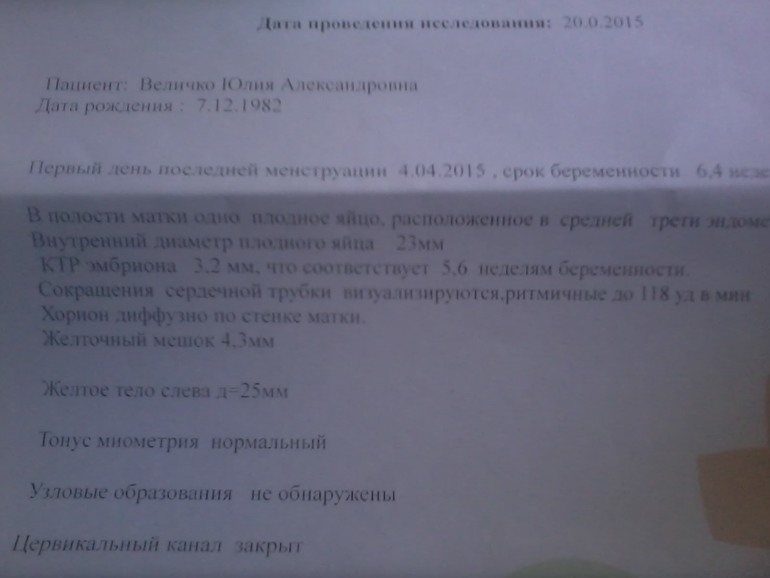

УЗИ, КТГ, доплерДевочки, подскажите, все ли в порядке с малышом? по УЗИ ставят меньше срок по развитию эмбриочика, это нормально? По М срок 6,5 недель. ПЯ=23мм, КТР=3,2мм, соответствует 5,6 недель, жетлочный мешочек =4,3мм. в ЛЯ-ЖТ=25мм. Сокращение сердечной трубки визуализируется ритмичное 118 уд. в мин. Как-то мало мне кажется, у многих девочек 140-160 уд. в мин. Стоит беспокоится? Узистка сказала, что это нормально, просто срок еще маленький и что можно уже становится на учет в ЖК.